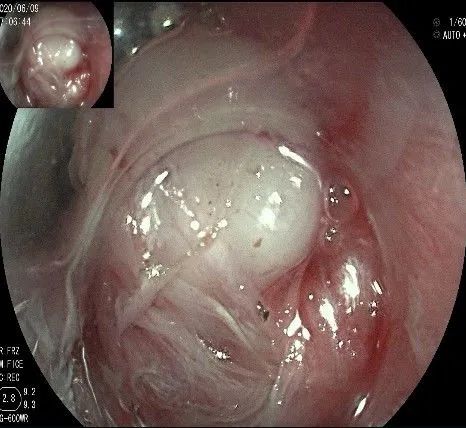

剥离接近完成,最后连接的薄层组织。

瘤子完整切除,随透明帽吸出的时候脱落到左侧会厌部,当时我们团队的麻醉、护理等人员都捏了一把汗,因为是静脉全麻没有插管,离声门太近了,一不小心进入气道会形成气管异物,造成严重后果!迅速换用鳄齿钳钳夹牢固,顺利取出!

完整的瘤体,呈不规则形状,长约2.0cm,宽度约0.8cm,有一定厚度,触之韧,像一颗白色的肾,表面有血管网。尽快浸泡送检。